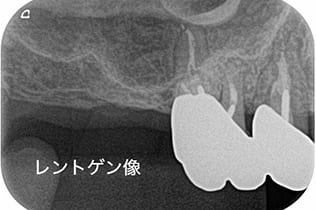

- 診査診断

歯茎の腫れを確認し、CT、レントゲンで確認し、根の先に問題があることを確認します。